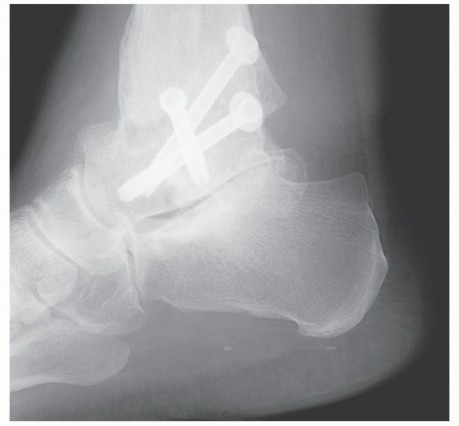

DEFINITION Triple arthrodesis is a procedure performed to restore and maintain physiologic hindfoot alignment…